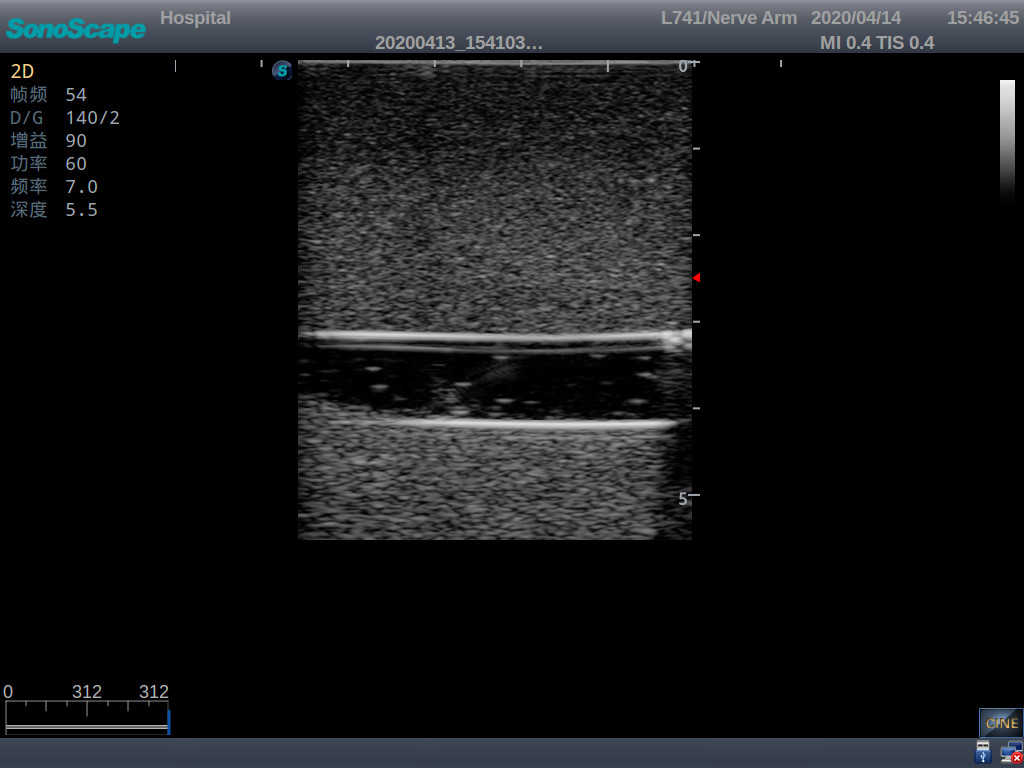

2) It can be used by real ultrasound machines

3) Clear and real images of the tissues and organs (basilic vein and superior vena cava)